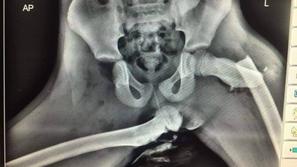

Rentgenski posnetek noge na armaturki

Pazljivo

Imela je noge na armaturki, takšne so posledice

Priljubljena navada marsikaterega sopotnika ima lahko grozljive posledice.